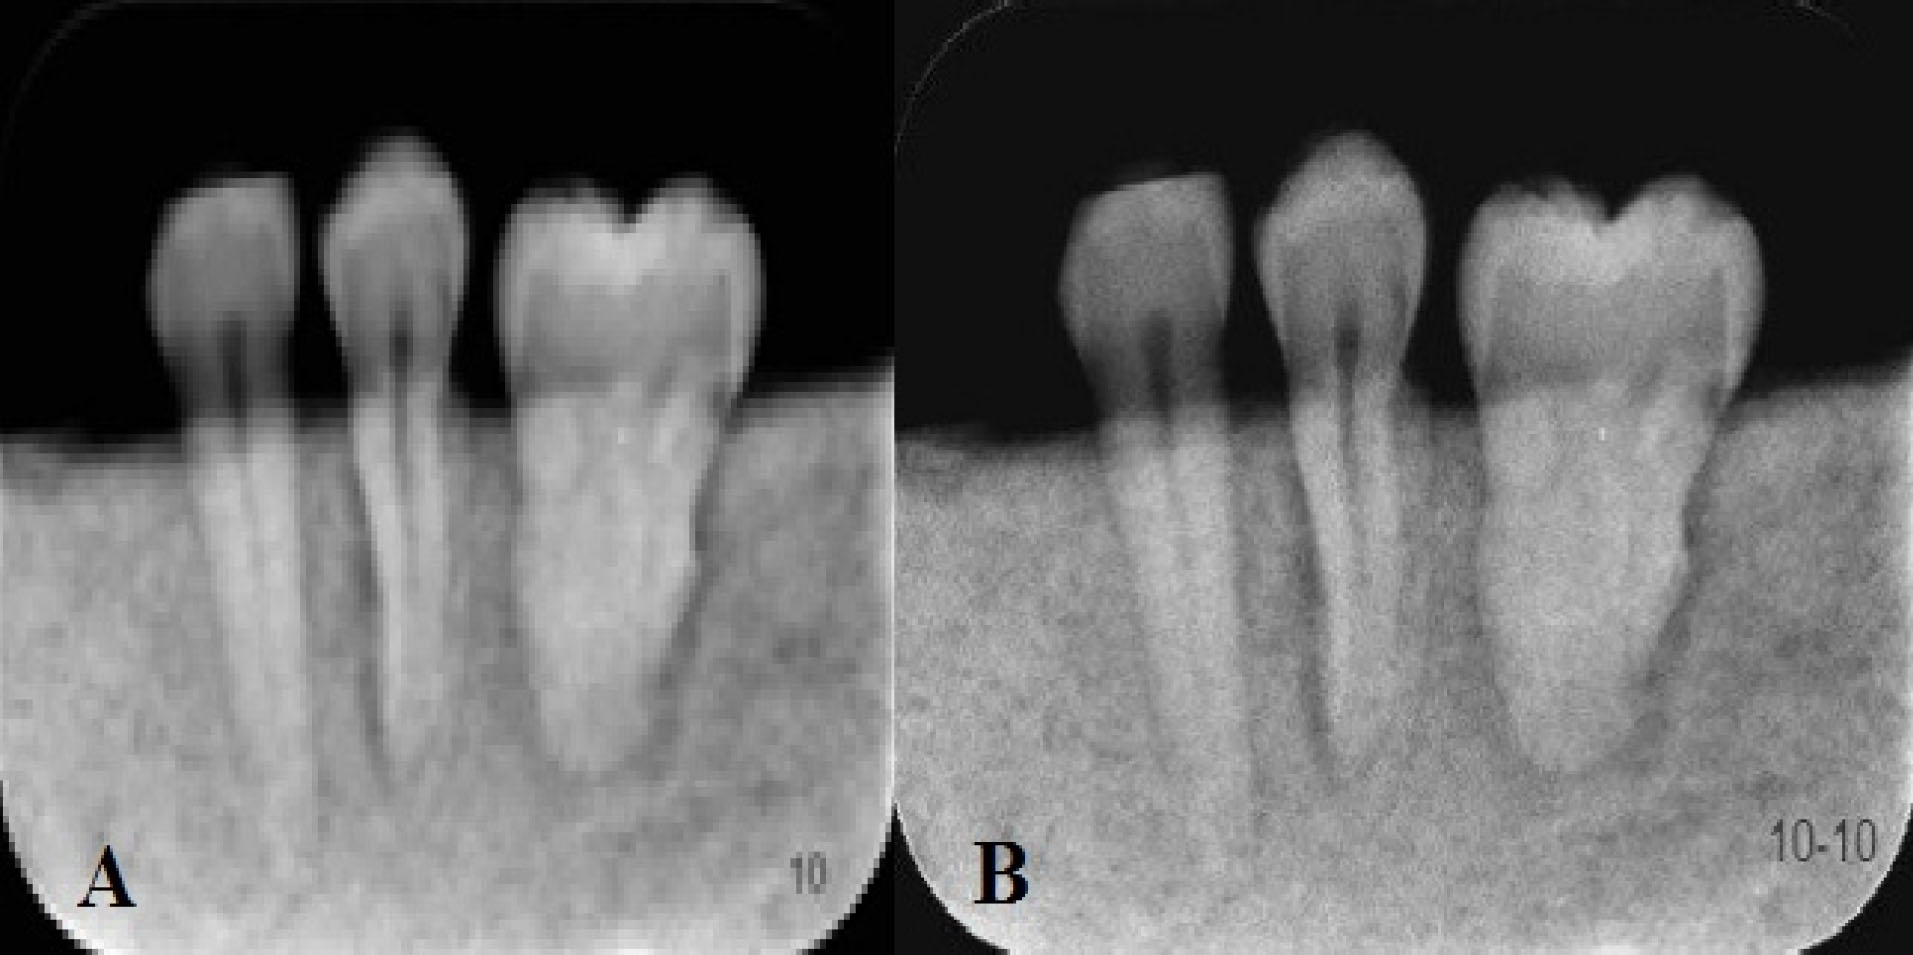

Figure 1.

Examples of original (A) and sharped (B) images captured with the Acteon system.